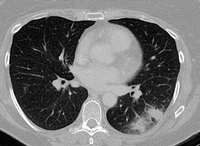

Sinal do "crescente aéreo" em aspergilose pulmonar avançada

Do acervo do Dr. P. Chandrasekar; usado com permissão

Veja esta imagem em contexto nas seguintes seções: